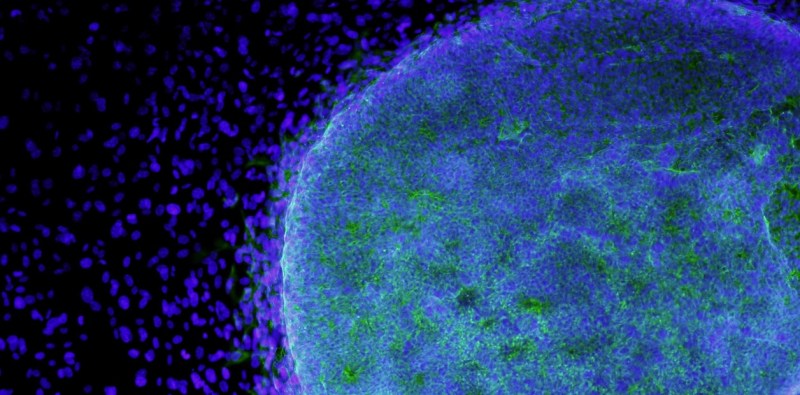

La entrada IRB la inhibición de la proteína p38 reduce el crecimiento de tumores de pulmón aparece primero en Revista NUVE.

Leer más: IRB la inhibición de la proteína p38 reduce el crecimiento de tumores de pulmón